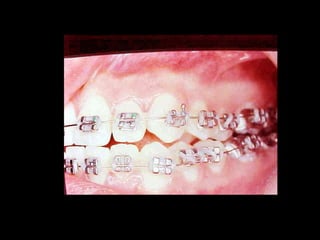

La paciente muestra una franca disgnatia, clínicamente

observamos malposición dentaria secundaria a la falta de

armonía máxilomandibular.

Marcada Clase III

Hábito Lingual

Sobremordida horizontal: –1.5 mm

Sobremordida vertical: + 1 mm.